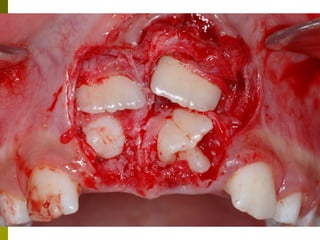

Οδοντικό τραύμα στα πρόσθια δόντια

 Όσο μικρότερο το παιδί, τόσο οι

πιθανότητες για βλάβη στο σπέρμα του

μόνιμου δοντιού είναι μεγαλύτερες

 Συχνότερα σε εμβυθίσεις, ολικές

εκγομφώσεις.

Οδοντικό τραύμα σταπρόσθια δόντια  Όσο μικρότερο το παιδί, τόσο οι πιθανότητες για βλάβη στο σπέρμα του μόνιμου δοντιού είναι μεγαλύτερες  Συχνότερα σε εμβυθίσεις, ολικές εκγομφώσεις.